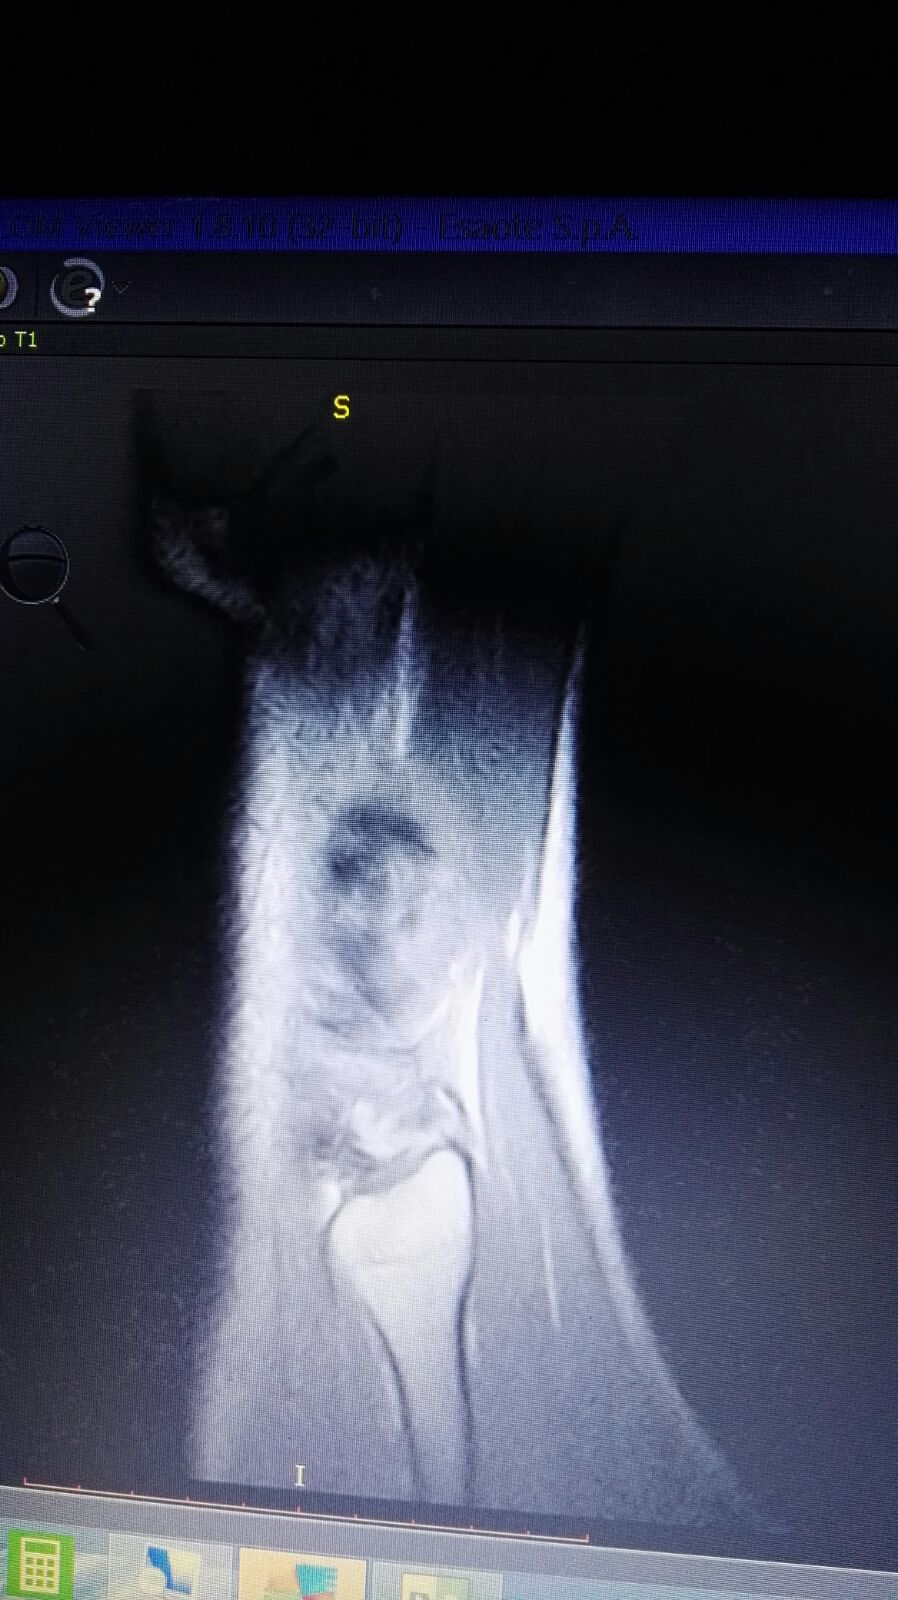

Salve mio marito circa un mese fa giocando a calcio si è fatto male il ginocchio. Essendo fuori per lavoro e riuscito solo a farsi una RSM LE mandi le foto se gentilmente può vederle. Lui è in addestramento per una missione volevo sapere se in un mese può farcela a guarire grazie mille.

IMG-20180301-WA0034.jpg

[ 185.66 KiB | Osservato 1320 volte ]